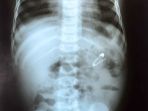

Mengerikan! Ini 10 Benda Aneh yang Ditemukan Di Perut Manusia, Ada Paku Hingga Ponsel

Tidak hanya makanan ada berbagai macam barang seperti baterai ponsel, paku hingga gunting pernah ditemukan dalam perut manusia.